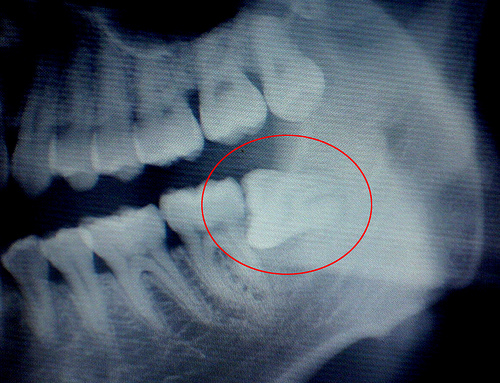

2、侵犯邻牙:通常患者不自知,而由牙医以X光诊断得知。通常智齿萌发的空间不足,而会倒在第二大臼齿上,因而造成第二大臼齿清洁不易,甚至是牙齿部分吸收的现象,造成患者不舒适或牙疼。

4、阻生齿:通常这是更讨厌的一种,牙医会觉得很难搞定,但病人却不一定有感觉,因此忽略了。这一种类型的牙齿,通常埋在齿槽骨的里面,如果会痛,或是诊断会有病灶发生的时候,就需要拔除了。推荐阅读:郑州市口腔医院拔智齿多少钱